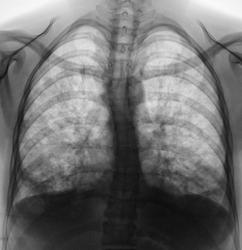

Результат выдали. Первая "флюшка" за апрель 2011 год, вторая - март 2012 год.

Потом, правда, лечащий доктор попросил, чтобы на всякий случай сделали "снимочек ОГК", так как пациентка подкашливает, да и "температурка" чуть выше 37 градусов.

Ну, сделали "рентгенограммку"...

Резко усилен лёгочный рисунок в верхних, средних и нижних полях с обеих сторон, обогащён за счёт очаговоподобных теней без чётких контуров. Корни лёгких расширены, малоструктурны. Дуги соr нечёткие за счёт суперпозиции изменённого лёгочного рисунка. Анамнез.

Флюшка делалась, когда пациентка была здоровенькая в ортоположении.

Рентгенограмма и томограммы произведены были в положении лежа, и поза у пациентки вынужденная, она действительно не может лежать на спине, болевой синдром, лежа на спине действительно очень сильный. По всей видимости, "прогрессирование сколиоза", больше вызвано анталгической позой.